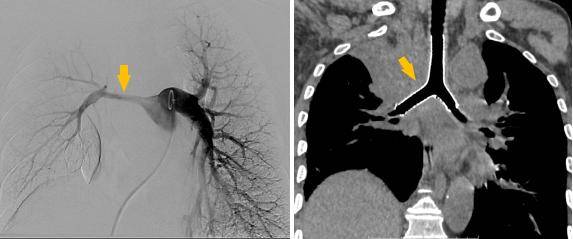

术前受压变窄的右肺动脉和中央气道

手术过程

同期置入支架后狭窄明显改善